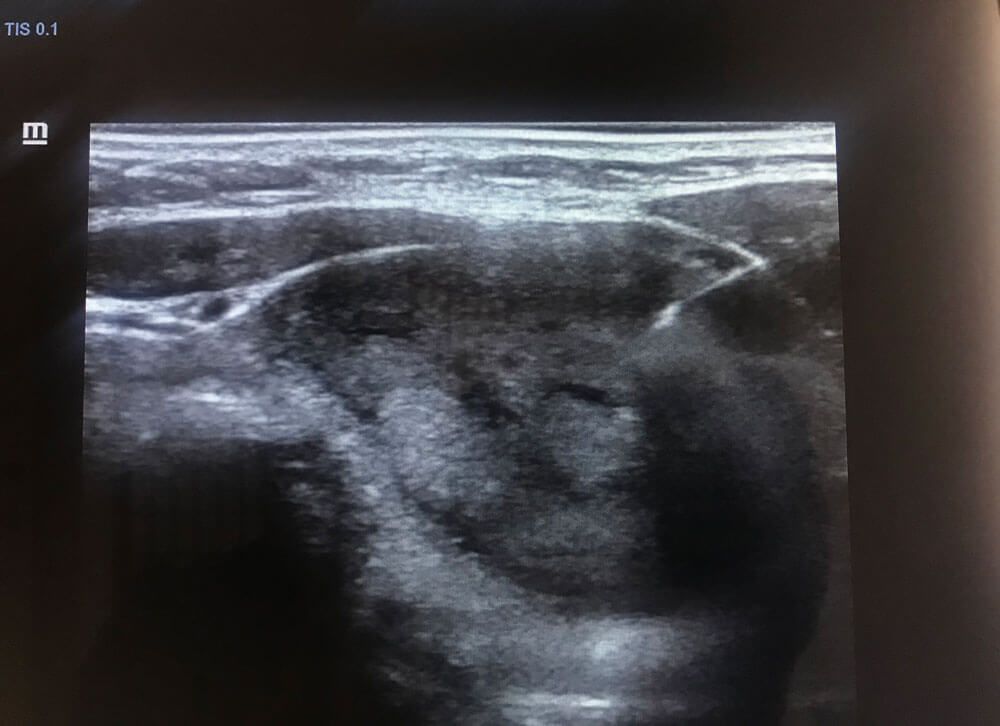

Realizamos

ultrasonidos

convencionales, gestacionales, pediátricos, especializados, entre otros. También aplicamos estudios con